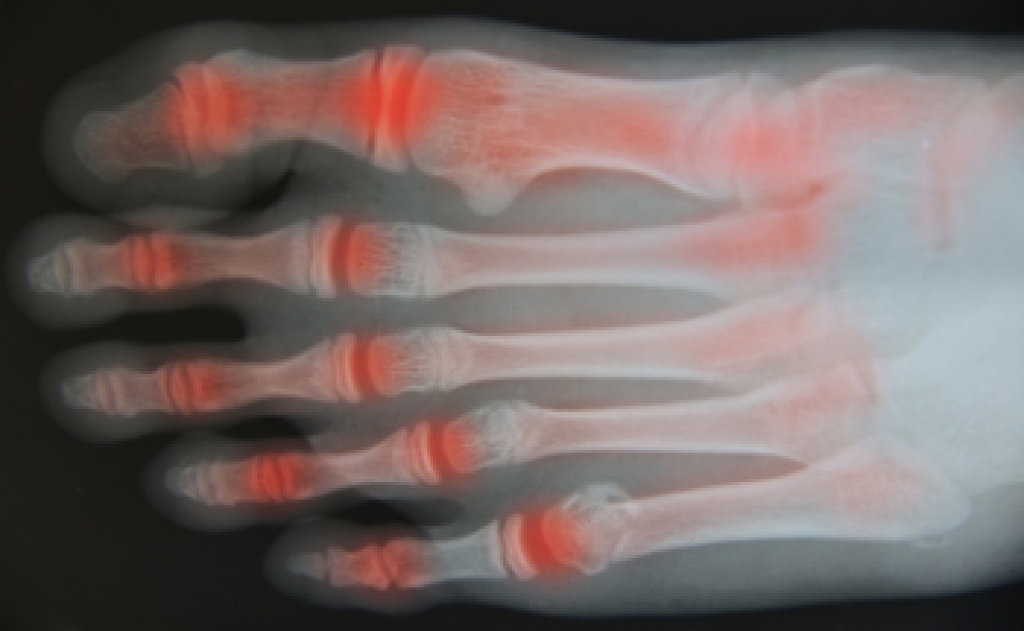

Psoriatic arthritis (PsA) is a chronic autoimmune disease that affects the joints, including those on the feet. It typically affects people who have a skin condition called psoriasis. When PsA affects the feet, it produces symptoms such as painful toe swelling, joint stiffness, pain in the heels and soles of your feet, and dented or crumbling toenails. The condition has a pattern of flaring up and then subsiding. Your podiatrist can be an important part of your healthcare team when it comes to dealing with PsA in the feet. A podiatrist can help you find comfortable shoes and orthotics, maintain your mobility, and relieve symptoms during a flare up. To learn more, speak to a podiatrist today.

Arthritis is a joint disorder that involves the inflammation of different joints in your body, such as those in your feet. Arthritis is often caused by a degenerative joint disease and causes mild to severe pain in all affected areas. In addition to this, swelling and stiffness in the affected joints can also be a common symptom of arthritis.